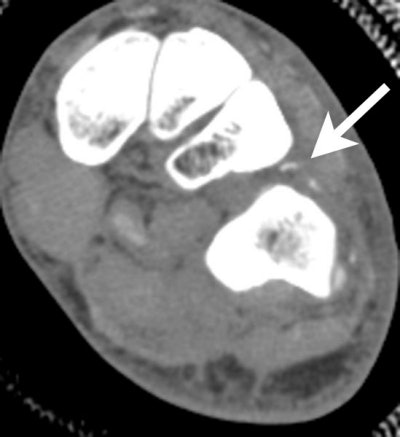

Axial FSEIR. Interstitial tearing of the popliteus muscle is seen. Popliteus muscle injuries also occurred in several athletes as an isolated injury. |